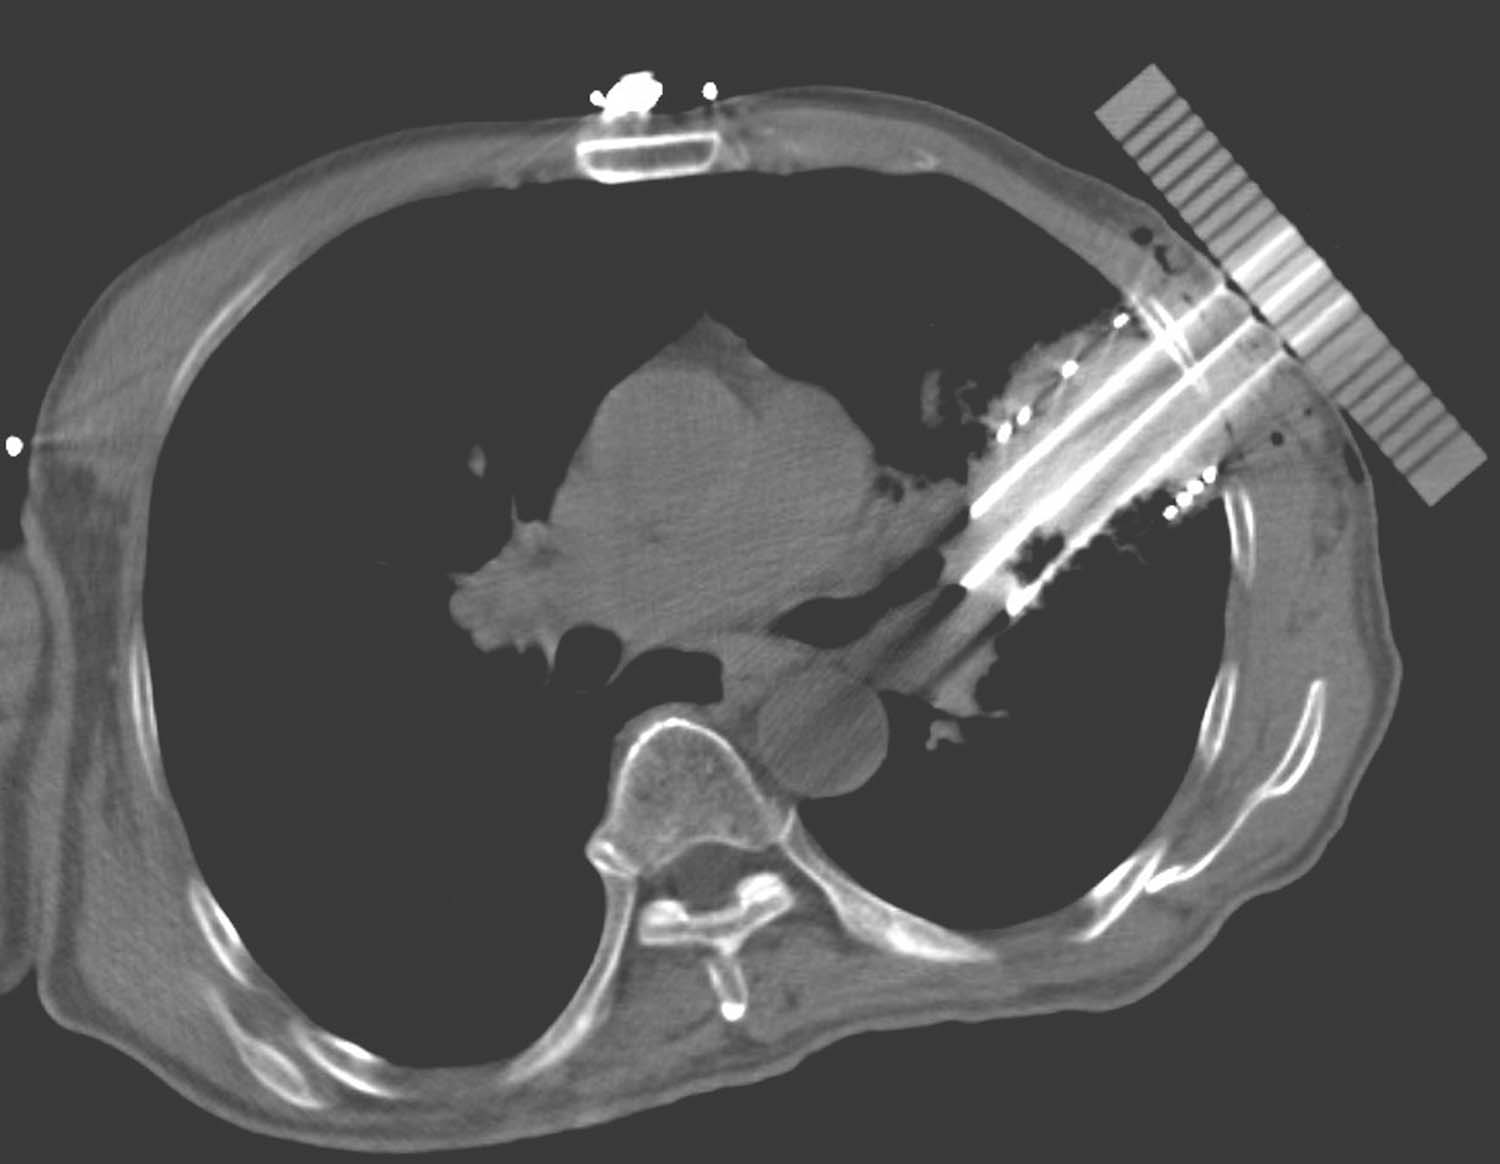

患者取与术前CT扫描相同体位,真空负压垫固定体位,防止穿刺过程中因体位变动给穿刺带来的不利影响。将导航支架与CT碳纤维床板相连接,以0.5cm层厚扫描,选取病灶中心层面,将一个预定进针点在皮肤表面做出大十字标记,消毒、铺巾、局麻,安装模板,用激光灯校准模板,使激光灯的 x 轴和 y 轴投影与模板表面的标记线相重合,利用数字化角度仪或者水平仪调整模板的角度和方向,使模板在 y 轴方向的角度为零,调整 x 轴方向的角度,与术前计划保持一致。选择病灶中心层面,参考术前计划,将数根穿刺针抵达皮肤表面,扫描观察针尾走行方向,再次校准模板,然后测量进针的深度,完成该层面的进针,如果是肺等移动度较大的脏器,可以先插入2~3根固定针,将病灶与模板迅速“绑定”(图4-3-1),然后再依次完成其他层面的进针,如果遇到坚韧骨骼遮挡,使用捻针或骨钻打孔技术破骨插植,待完成所有层面的进针以后再植入粒子。

例1 患者男性,72岁,左肺鳞癌侵犯胸壁并同侧肺门淋巴结转移,T4N1M0。2018年1月16日行共面模板引导放射性粒子植入术(图4-3-2~图4-3-7)。

图4-3-3 模板引导,完成选择层面的进针

图4-3-4 依次完成其他层面的进针

图4-3-5 完成肺门病灶的进针